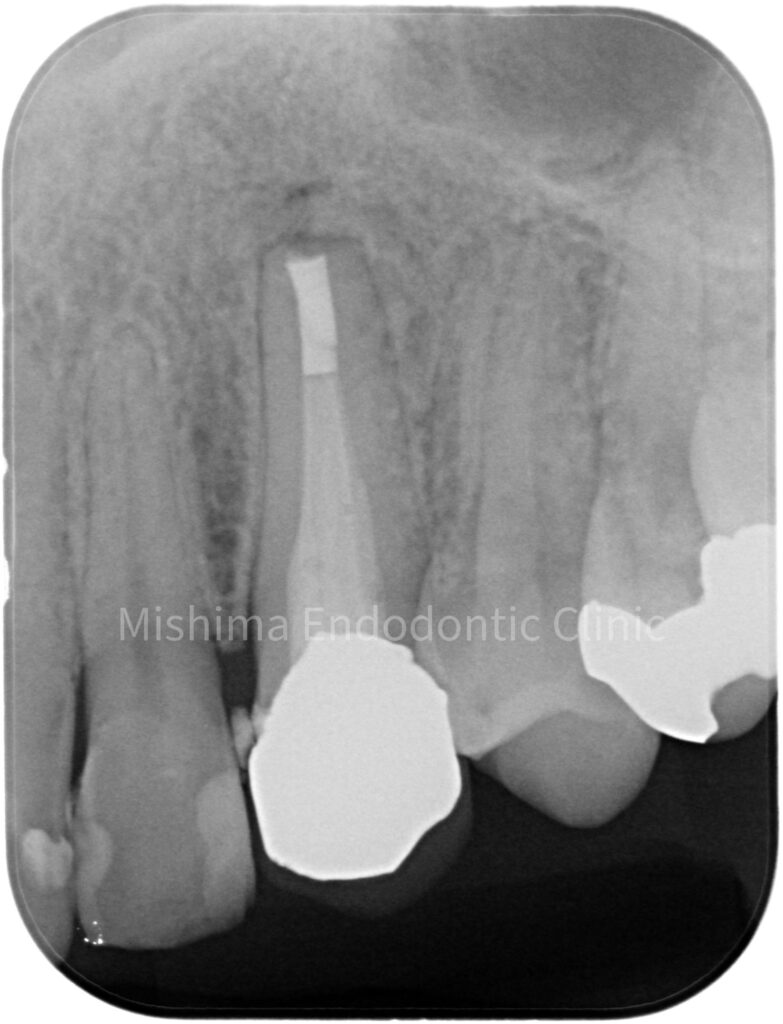

After

| 治療内容 | 23が既に根管治療が介入され仮封の状態で、サイナストラクト、自発痛を認めた。 根管治療を行うも症状の改善認めず、歯根端切除術へ移行。 |

| 治療期間・治療回数 | 3回 / 1ヶ月 |

| 治療費用 | 根管治療 121,000円 隔壁 5,500円 支台築造(ファイバー) 16,500円 歯根端切除術 99,000円 |